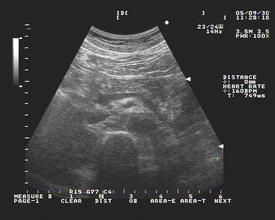

(3)腹部B超:可幫助診斷。B超掃描能發現胰腺水腫和胰周液體的積聚。還可探查膽囊結石,膽管結石。但受局部充氣腸袢的遮蓋.限制了其套用。